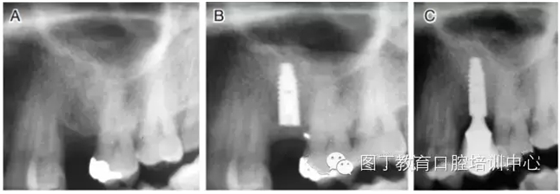

病例1 骨質(zhì)較充裕(圖3)

圖3